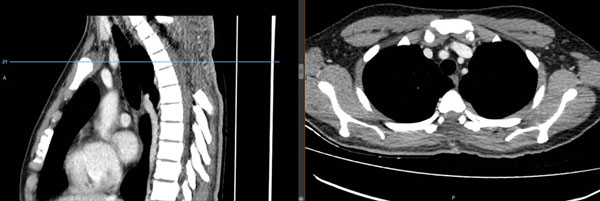

Se realizó laminectomía D2-D6 con exéresis macroscópicamente total del tumor de color amarillo pardo (Figura 2). El estudio anatomopatológico e inmunohistoquímico de la pieza operatoria fue linfohistiocitosis-enfermedad de Rosai-Dorfman. En el postoperatorio inmediato cursó con fiebre sostenida de 39°- 40° la que persistió por 3 semanas, cediendo en la cuarta semana. Se realizaron hemocultivos seriados, urocultivo, cultivo de líquido cefalorraquídeo con resultados negativos para infección. También presentó disminución de peso y dorsalgia, atribuidas a la postración. Por diagnóstico diferencial de síndrome paraneoplásico, se administró corticoterapia (prednisona 1 mg/kg) antes y después del acto quirúrgico. Posteriormente, y por sugerencia de Hematología, se agregó talidomida y dexametasona por 2 meses, además de tratamiento sintomático.

Figura 2. Tomografía computada de columna dorsal con contraste. Se evidencia laminectomía D2 – D6, no se observa lesión hipercaptadora de contraste sugerente de lesión neoproliferativa residual.

En la primera semana del postoperatorio no hubo mejoría neurológica. Luego, en las semanas siguientes, el paciente evolucionó favorablemente respecto al déficit motor, mejoró la sensibilidad y controló esfínteres.

Seis meses después de la cirugía continuó en rehabilitación y deambuló con apoyo, paraparesia 4/5, controló esfínteres y no presentó parestesias. Actualmente, el paciente recuperó la fuerza muscular 5/5.